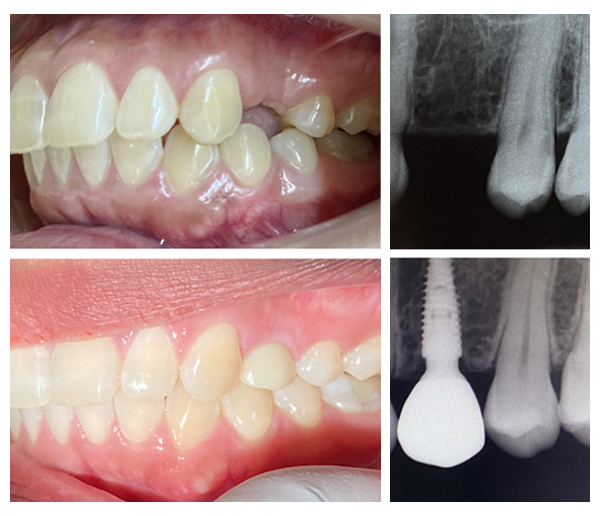

ภาพตัวอย่างการฝังรากฟันเทียม Neodent ในตำแหน่งฟันกรามน้อย